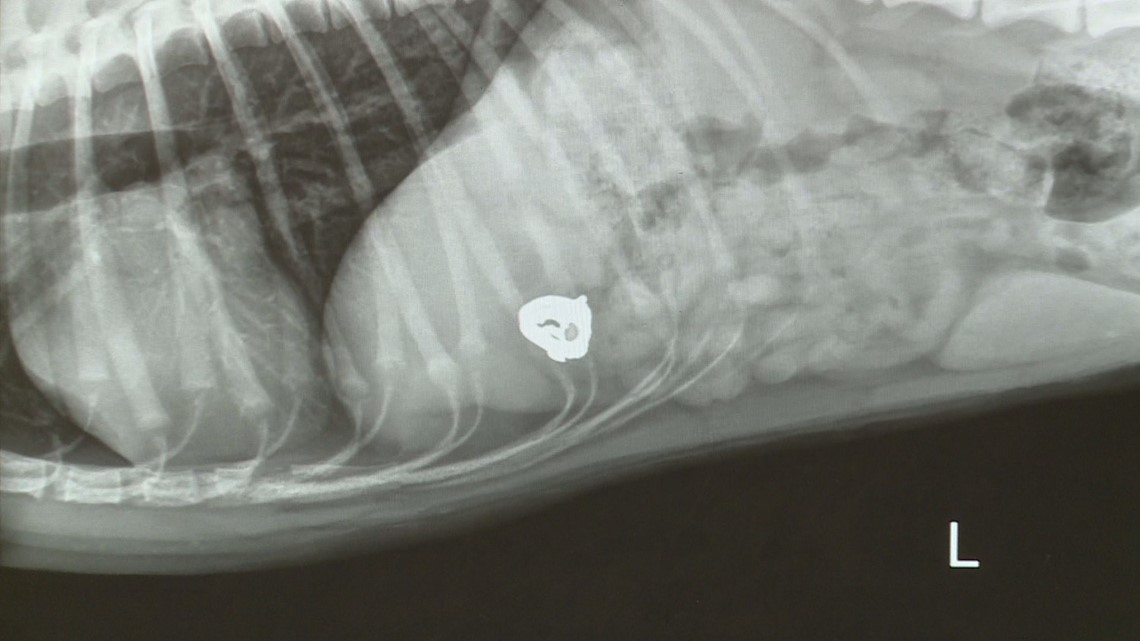

Dog swallows owner's engagement ring in South Africa; hospital shares X What To Do If Your Dog Swallows A Ring What to do if our dog ate onion rings. “don’t freak if your dog licks up a little glue,” says dr. First, find out how many pieces of onion rings. Timing and how you react is important. If the ring is small and you think your dog. First, try to assess the situation. The first thing to do is make. What To Do If Your Dog Swallows A Ring.